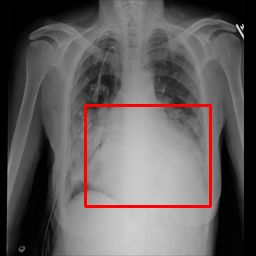

Deployments of artificial intelligence in medical diagnostics mandate not just accuracy and efficacy but also trust, emphasizing the need for explainability in machine decisions. The recent trend in automated medical image diagnostics leans towards the deployment of Transformer-based architectures, credited to their impressive capabilities. Since the self-attention feature of transformers contributes towards identifying crucial regions during the classification process, they enhance the trustability of the methods. However, the complex intricacies of these attention mechanisms may fall short of effectively pinpointing the regions of interest directly influencing AI decisions. Our research endeavors to innovate a unique attention block that underscores the correlation between 'regions' rather than 'pixels'. To address this challenge, we introduce an innovative system grounded in prototype learning, featuring an advanced self-attention mechanism that goes beyond conventional ad-hoc visual explanation techniques by offering comprehensible visual insights. A combined quantitative and qualitative methodological approach was used to demonstrate the effectiveness of the proposed method on the large-scale NIH chest X-ray dataset. Experimental results showed that our proposed method offers a promising direction for explainability, which can lead to the development of more trustable systems, which can facilitate easier and rapid adoption of such technology into routine clinics. The code is available at www.github.com/NUBagcilab/r2r_proto.